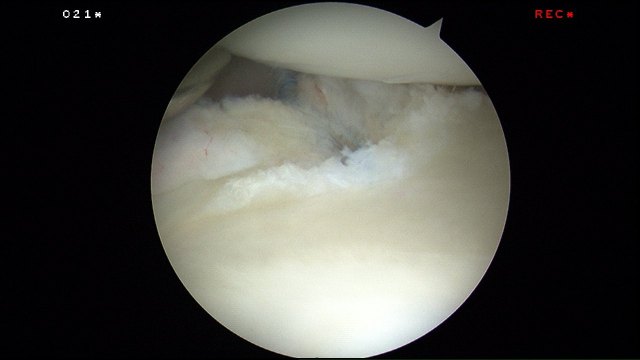

During key-hole surgery to his left shoulder, a tear in the posterior inferior glenoid labrum could be seen. This was the cause of his persistent vague shoulder pain.

The tear was delineated with an arthroscopic liberator and rasp.